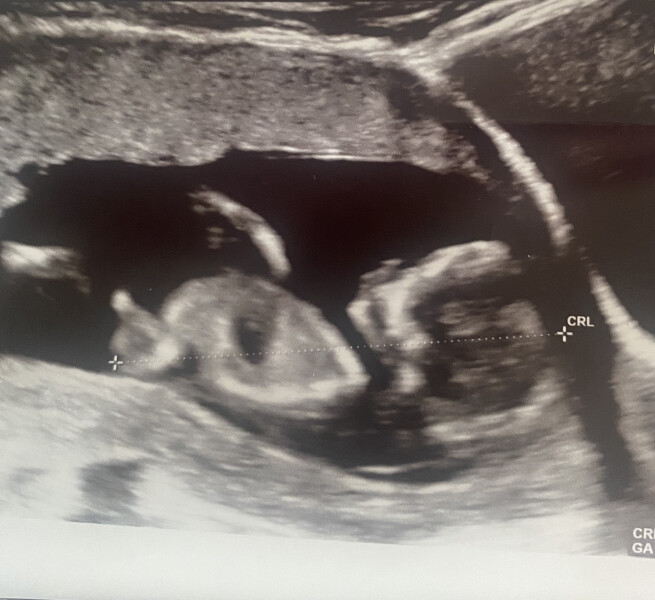

teddy2806 · 05/06/2022 11:14

Had my dating scan in the last week and official due date is 29th November 🥳 we don't plan on finding out the gender but happy to let people guess and Google everything possible, I just don't want professional confirmation 😂 anyone any guesses?

Bramblecrumble21 · 05/06/2022 21:11

Very cute teddy. Looks like it's pushing up at the probe with arms and legs, just like mine. It's great to see them move around so much. Just 2 weeks till my abnormality scan. I am now feeling flutters most days.